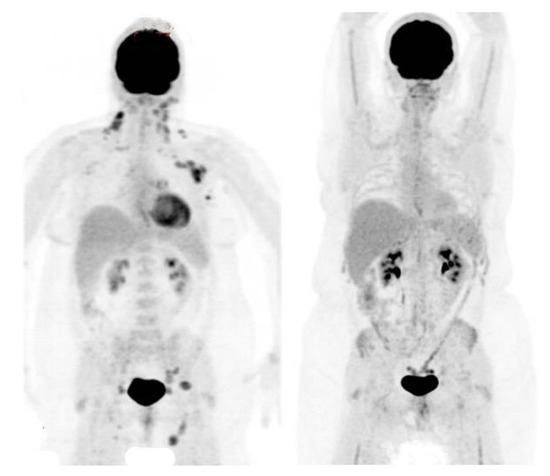

2.2. PET Response Assessment

4.3. PET Imaging